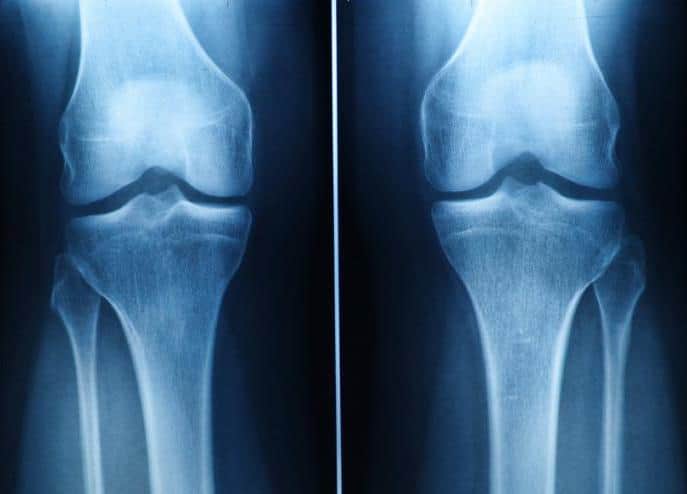

Limited Regenerative Capacity of Cartilage

Cartilage has limited regenerative capacity, and current pharmacological treatments offer only symptomatic relief. Patients who don’t respond to conventional therapies may undergo surgical procedures like arthroplasty or total joint replacement.